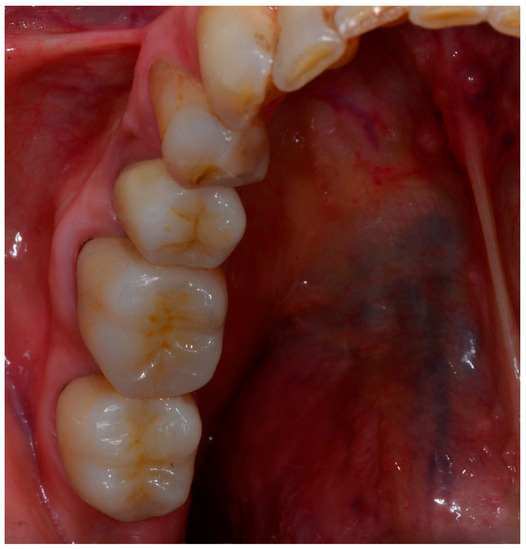

2. Materials and Methods

3. Results